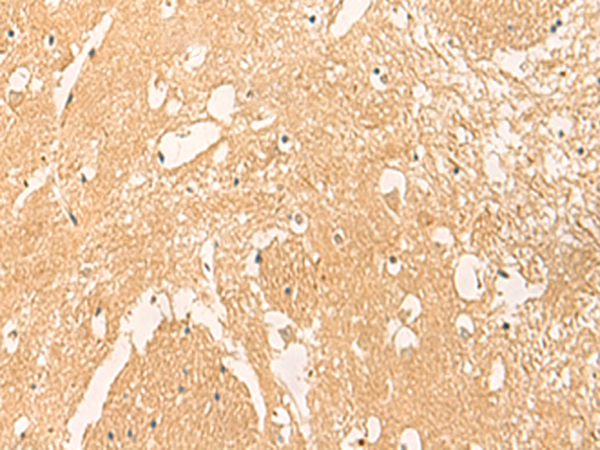

分类: 科研抗体货号: P09880别名: PDIR应用: WB,IHC反应种属: Human, Mouse, Rat

分类: 科研抗体货号: P09886别名: CHED; CHED1; CHED2; PPCD1; ZNF339; EUROIMAGE566589应用: WB,IHC反应种属: Human, Mouse

分类: 科研抗体货号: P09877别名: PTD017; S18amt; C6orf14; HSPC183; MRPS18-2; HumanS18a; MRP-S18-2应用: WB,IHC反应种属: Human

分类: 科研抗体货号: P09883别名: SS1; DRB1; HLA-DRB; HLA-DR1B应用: WB,IHC反应种属: Human